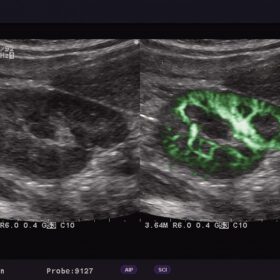

Ultrasound Aloka Prosound Alpha 6 – Image Gallery and Videos

Incredible Imaging Technology Bringing About High Versatility

- Broadband Harmonics(BbH)

- Adaptive Image Processing (AIP)

- Spatial Compound Imaging (SCI)

- eFLOW